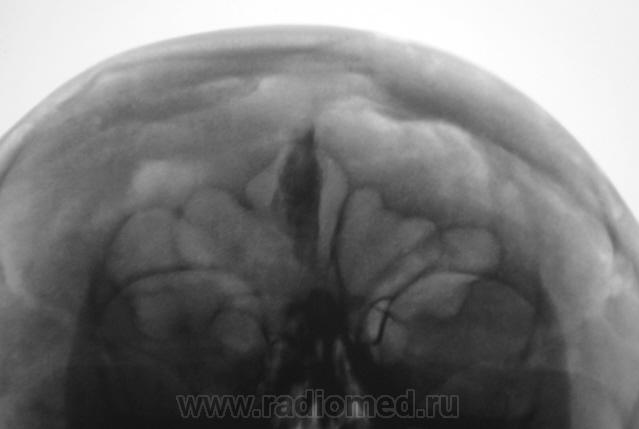

Пациент направлен на рентгенографию ППН по причине предстоящей операции «на глазах».

Обызвествилась не нужная часть мозга

Обызвествление серповидного отростка.

А, меня, что-то смутила чешуя лобной кости...

Действительно, лобная кость какая-то "кучерявая", а в боковой проекции не доснимали?

Прямая проекция.

Вены широковаты и боковые лакуны также выражены. Возможно на фоне остеопороза. Возраст, вероятно, немолодой.

Гиперпневматизация лобных пазух. Обызвествление серповидного отростка. Вероятно, повышение внутричерепного давления (сосудистый рисунок). Искривление носовой перегородки вправоsmiley. На нижнюю треть верхнечелюстных пазух "наслоились" пирамиды височных костей.